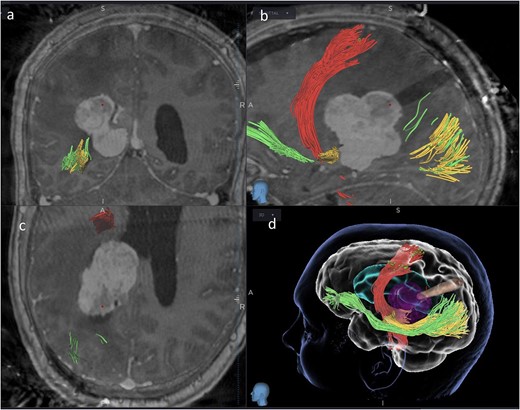

Subsequently, a tsMIPS approach was performed through the intraparietal sulcus. A tubular retractor (NICO BrainPath®) was cannulated 30 mm deep, directly onto the lesion. Following docking of the tubular retractor, an intra-operative CT scan (O-ARM®) was performed, and the resulting images were fused with pre-operative MRI and tractography. The port was identified at the centre of the lesion, with air acting as contrast (Fig. 3). The tumour was centrally debulked, outer sides rolled inwards, and capsule disconnected.

Coronal (a), sagittal (b) and axial (c) views of the merged images from intra-operative CT scans (O-Arm) with pre-operative MRI tractography. The tubular retractor is in situ. (d) Virtual 3D reconstruction of the tubular retractor (brown) in the merged images and its relationship with the tumour (purple), the CST (red), the IFOF (green), and the OR (yellow).